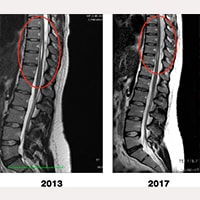

Poniżej można zobaczyć porównanie obrazów MRI przedoperacyjnych i pooperacyjnych, na których widać znaczące pomniejszenie się jamy syringomielicznej.

Jama syringomieliczna pacjentki, porównanie między obrazami RM z 2013 r. i z 2017 r.